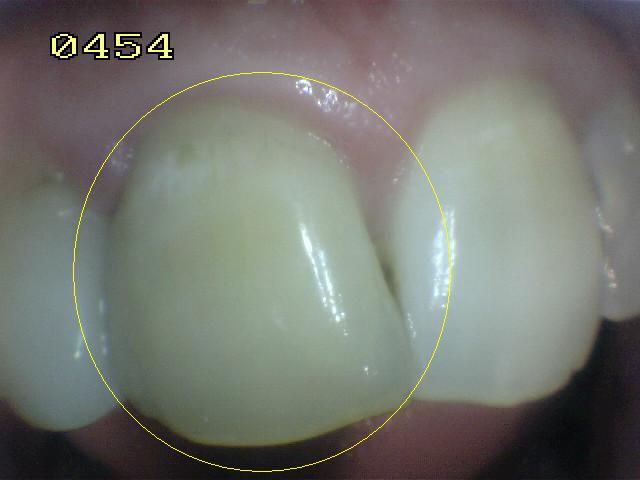

| La

tinción interna

de la dentina por hemorragias intra-pulpares

(traumatismos o biopulpectomias deficientes) puede decolorar los

dientes de adentro hacia afuera.

El blanqueamiento interno puede

solucionar este problema. Ver imagen derecha